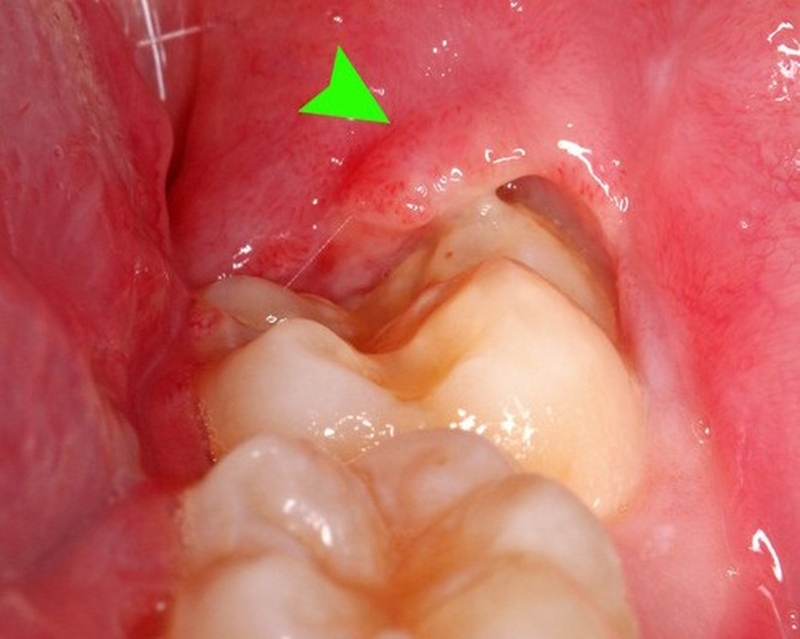

Nếu ngay từ giai đoạn đầu không được chữa trị dứt điểm và để kéo dài thì tình trạng viêm lợi sẽ ngày càng nghiêm trọng hơn khi phần lợi và xương hàm bị xô ra phía sau, tạo ra lỗ hổng cạnh chân răng. Đó sẽ trở thành địa điểm tích tụ thức ăn thừa và vi khuẩn dẫn đến chân răng bị nhiễm trùng.

Nhiều trường hợp, răng khôn mọc trong thai kỳ kết hợp với sự nhạy cảm của mô lợi rất dễ gây cho bà bầu bị viêm lợi trùm. Gây khó chịu và ảnh hưởng tới sinh hoạt hằng ngày, sức khỏe của mẹ bầu và thai nhi.

Cách chữa viêm lợi cho bà bầu không gây tác dụng phụ 2Viêm lợi trùm gây khó chịu và ảnh hưởng đến sức khỏe của mẹ và thai nhi